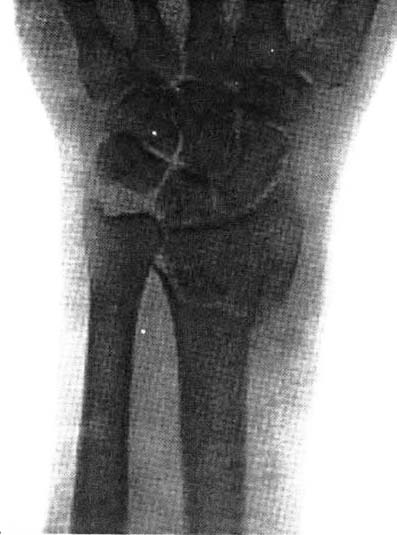

図2.橈骨骨折(Colles骨折)[8].

早期から積極的に撮影されたのはやはり骨折,脱臼で,例えばColles骨折のように従来から臨床的に良く知られていた骨折の所見がX線像で確認されると同時に[1](図2),Jones骨折に代表される新たなタイプの骨折や[→原著論文],X線写真でしか診断できない "X-ray fracture" の存在が知られるようになった.X線以前には「捻挫はしばしば骨折よりも重症」という認識があったが,これは単に骨折が誤って捻挫と診断されていたためであることもわかった[2].